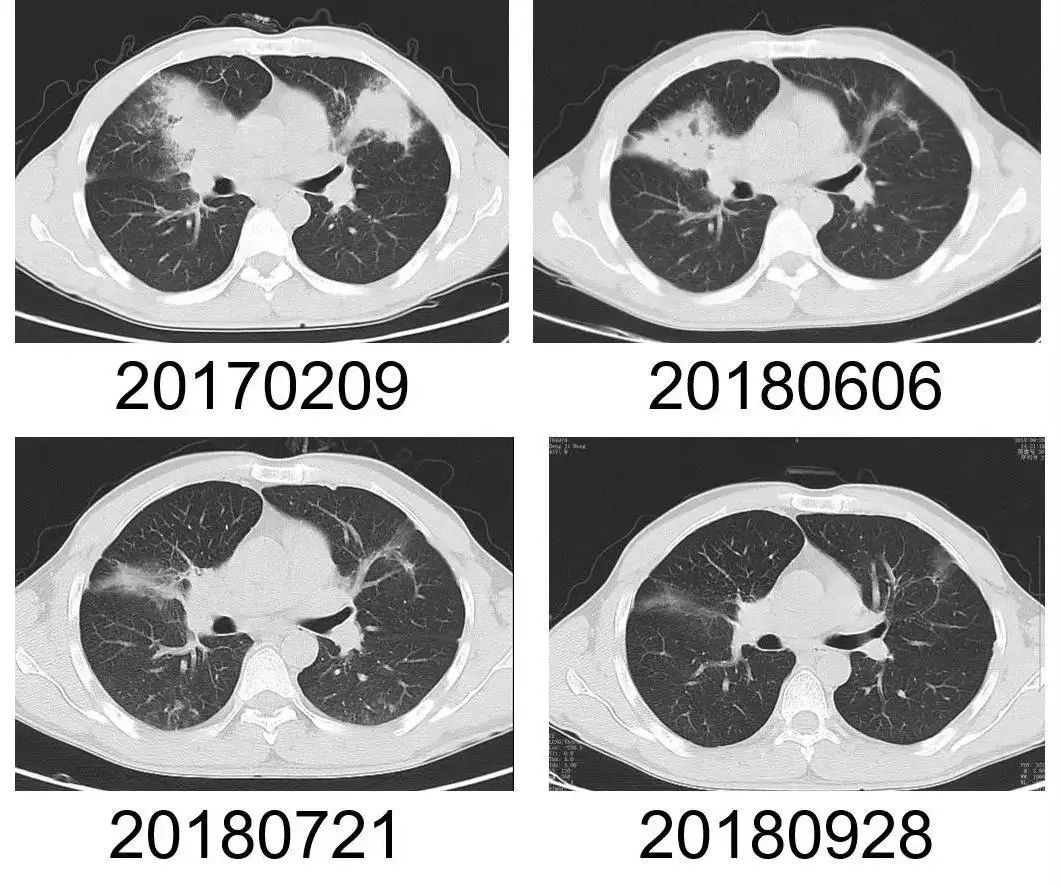

∆ 李先生的肺部CT,经对症治疗后,肺部感染灶明显缩小。